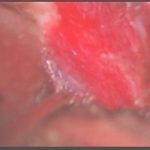

術中写真

摘出 前